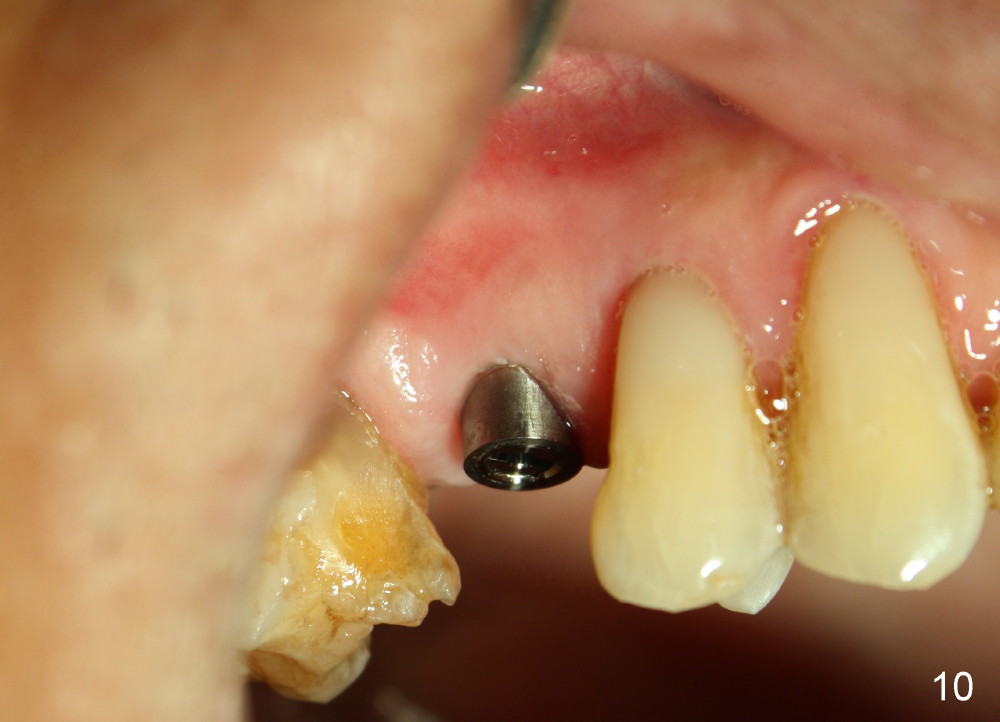

A 72-year-old man is a bruxer with #3 cusp fracture with chronic periapical radiolucency (Fig.1 *) and #4 acute crack.  It appears reasonable to take care of emergency (#4 extraction and immediate implant (Fig.3-7: 4.5x20 mm, 45 Ncm)) followed by root canal therapy or extraction for #3.  Eight (Fig.8) and 14 (Fig.9-11) days postop, the patient is doing fine and the wound heals normally.  But he does not agree any treatment for #3, since it is asymptomatic in spite of a fistula associated with the tooth (Fig.8,9 >).  Three months postop, the patient is still asymptomatic and is ready for #4 restoration since the tooth #28 cracks.  Follow-up PA shows the persistent distal gap (Fig.12 >, as compared to Fig.4), accompanied with crestal bone resorption (*).  Clinically the implant has mild mobility and light tenderness. The patient still refuses #3 treatment. It appears that the implant has failed to osteointegrate.  In brief, do not place an immediate implant next to active infection.